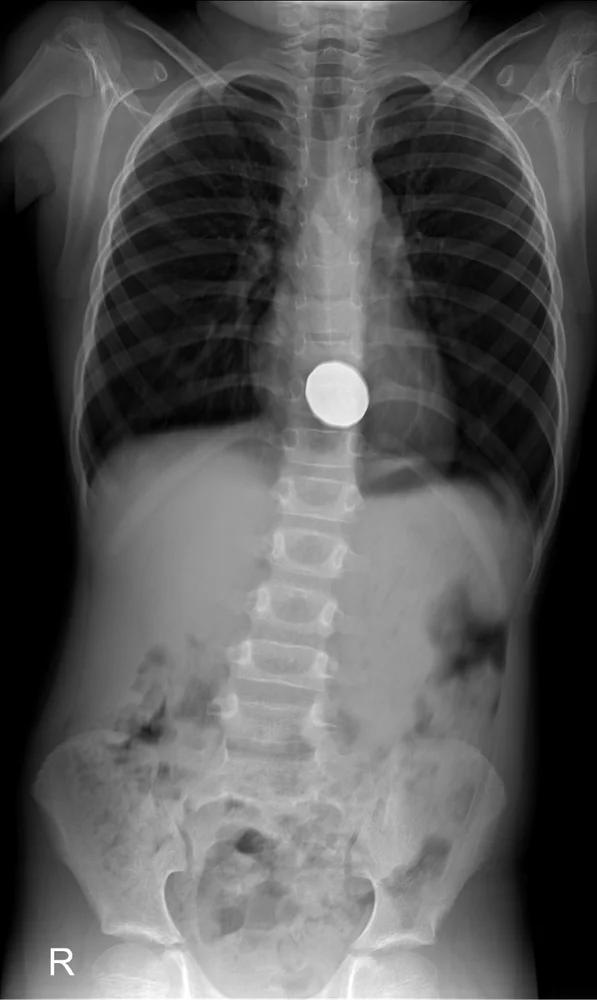

במקומות רבים בעולם מטבעות הם אחד החפצים הנפוצים ביותר שנבלעים על ידי ילדים. ילד בן 4 בבריטניה בלע מטבע של 2 פאונד. לאחר צילום רנטגן נמצא המטבע בקיבתו, ולמזלו, הוא עבר החוצה בצורה טבעית.